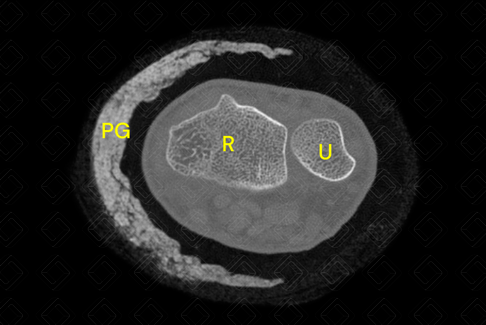

Texto alternativo para a imagem Figura 2. Créditos: Athena Hub/Medical Harbour

Legenda: C = capitato; E = escafoide; H = hamato; P = piramidal; [cms-watermark] [cms-watermark] [cms-watermark] [cms-watermark] PG = prótese gessada; R = rádio; S = semilunar; T = trapézio; TT = trapezoide; [cms-watermark] [cms-watermark] U = ulna.